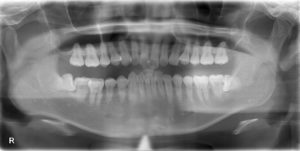

画面向かって左下の親知らずです。

横向きにはえていましたが、麻酔時間含め30分で抜歯終了しております(^^♪